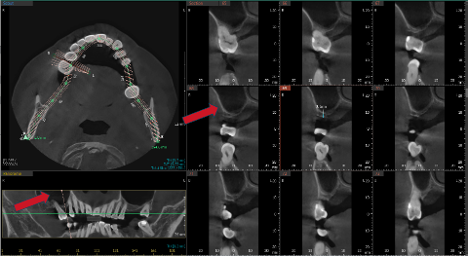

After